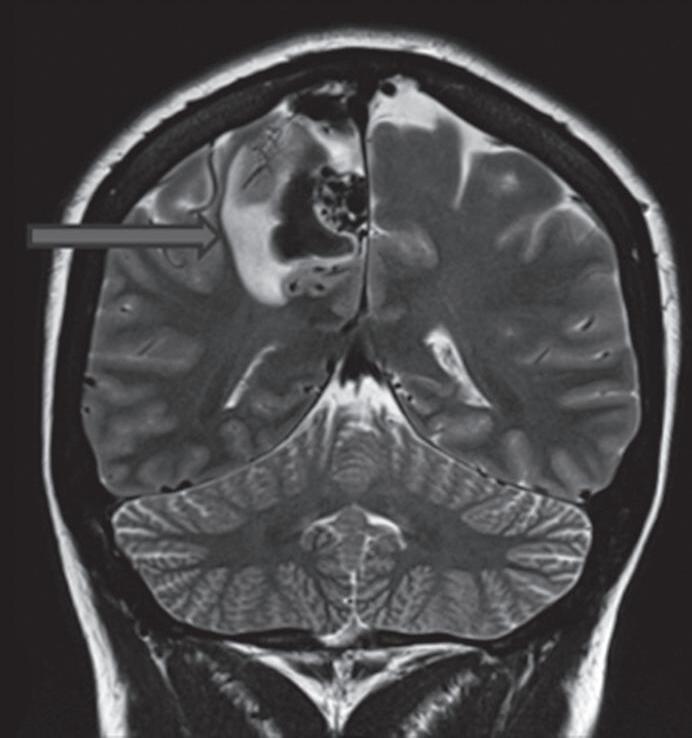

Fig. 1-14. RNM encéfalo, T2 axial (a) e coronal (b), demonstrando MAV grau 2 no lobo parietal esquerdo.

Arteriografia cerebral (c) AP e (d) em perfil, demonstrando a irrigação pelos ramos da artéria cerebral média (ACM) e anterior (ACA), com drenagem pela veia de Labbé, no seio transverso sigmoide.